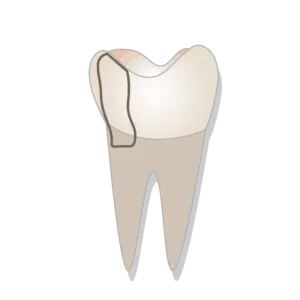

What is a Fractured Cusp?

A fractured cusp is a common dental injury that occurs when a piece of a tooth’s chewing surface breaks. The break or crack affects a portion of the tooth called the cusp.

Cusps are the raised areas on a tooth’s chewing surface that help grind food. Each tooth has at least one cusp, and most molars have four or five.

A cusp can fracture for many reasons, including tooth decay or injury. The severity of symptoms it will cause depends on the extent of the crack and whether the dental pulp (inner soft tissue) is exposed.